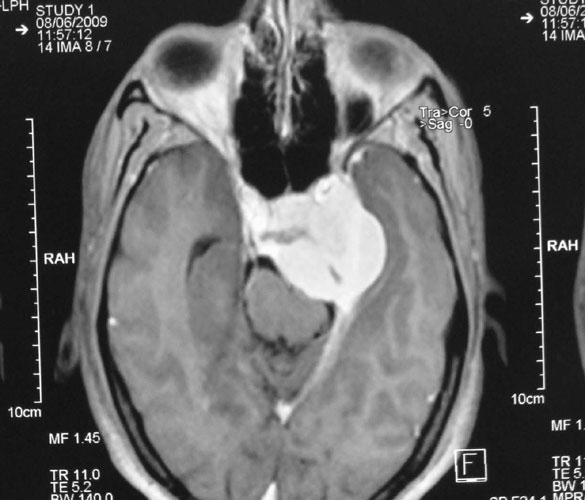

Pituitary Tumours

Pituitary is a small gland in the midline of skull base that has important role in maintaining hormonal milieu of the body. Tumors arising from pituitary present as gradually worsening partial blindness (‘field defects’), headache and endocrine abnormalities, commonest being acromegaly. Management involves a teamwork, with close association of neurosurgeon, endocrinologist and radiation oncologist. Surgery (through the nose or transcranial) is required to excise the tumor, followed by radiotherapy and management of hormonal deficiencies